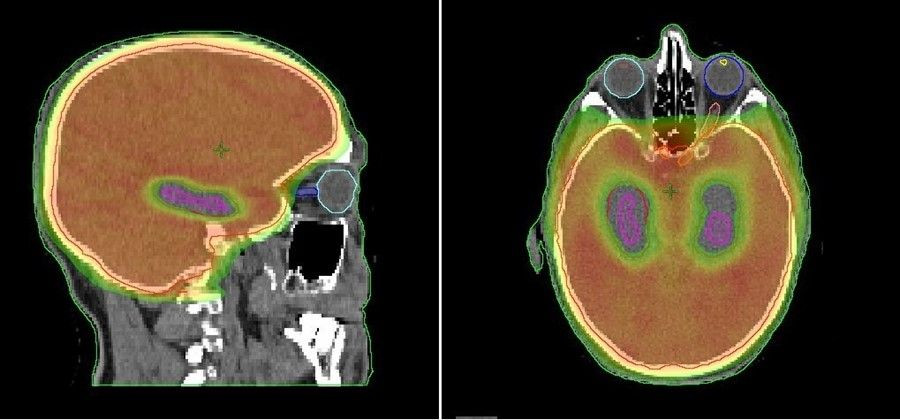

El Servicio de Oncología Radioterápica del Hospital del Mar de Barelona ha coordinado un estudio que demuestra que proteger el hipocampo de la radiación en aquellos pacientes con cáncer de pulmón de células pequeñas que tienen que someterse a radioterapia para evitar la aparición de metástasis en el cerebro es una "estrategia válida" para proteger su memoria sin afectar sus probabilidades de supervivencia.

Con la protección del hipocampo, una pequeña zona situada en la región central del cerebro vinculada, entre otras cosas, a la memoria y al aprendizaje, permite reducir "hasta cinco veces" la afectación sobre la memoria en los pacientes estudiados.